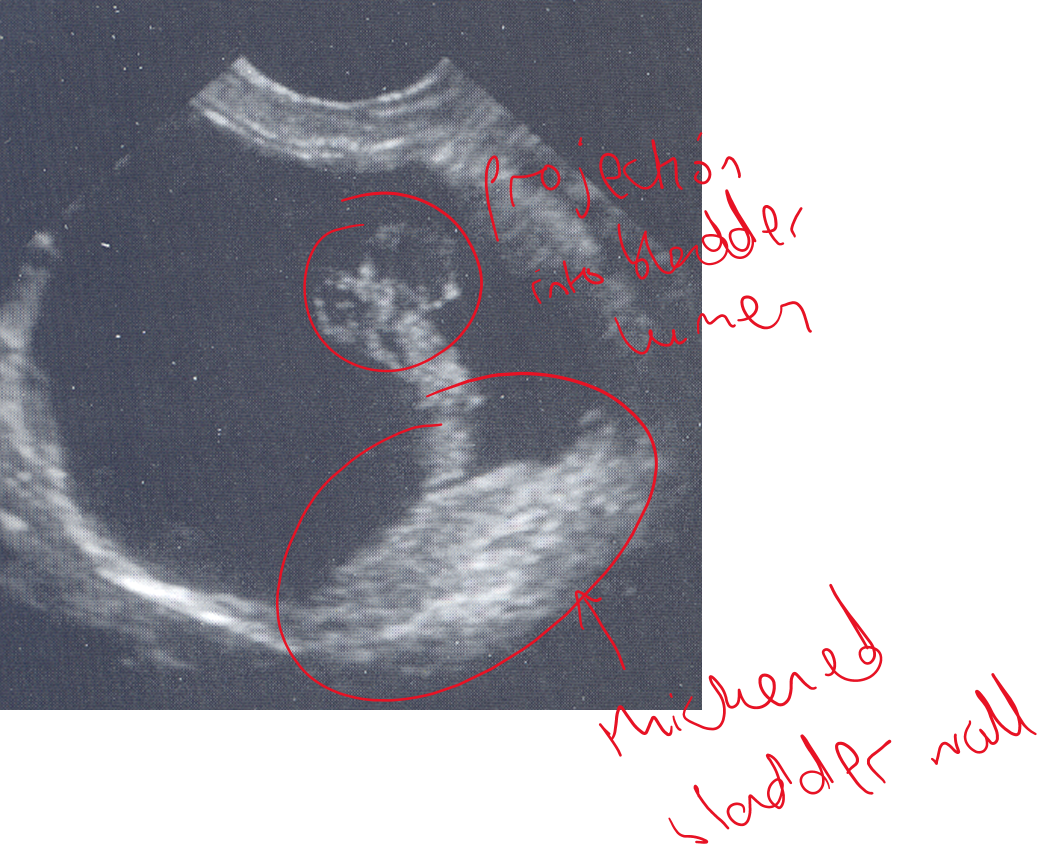

What is being shown in this bladder?

Cystolith (bladder stone) —> casting acoustic shadow

What is being shown in these bladders?

L —> thickened wall with a hyperechoic lesion arising from the wall —> consistent with a bladder wall mass

R —> thickened and within the lumen we can see hyperechoic areas which may be a mass or could be blood clots.

How do you use a doppler to tell the difference between a blood clot vs a tumour?

Blood clot has no blood flow, tumour does